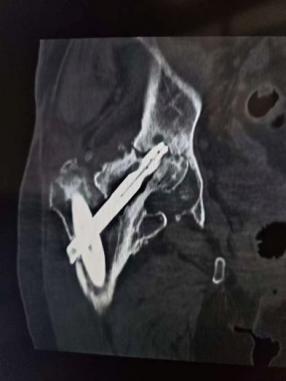

术后X线片

在王争刚主任医师主刀下,手术团队精准取出移位的内固定物,细致处理坏死骨组织,并在骨质缺损区域进行精确重建,最后植入人工髋关节假体。整台手术仅用时1小时,术中出血量少,假体安放位置理想,为患者后续的快速康复奠定了坚实基础。

术后,谈大妈在医护团队指导下开始了系统康复训练。令人欣喜的是,术后第13天,她已能扶着助行器独立行走,疼痛完全消失,髋关节功能得到显著恢复。